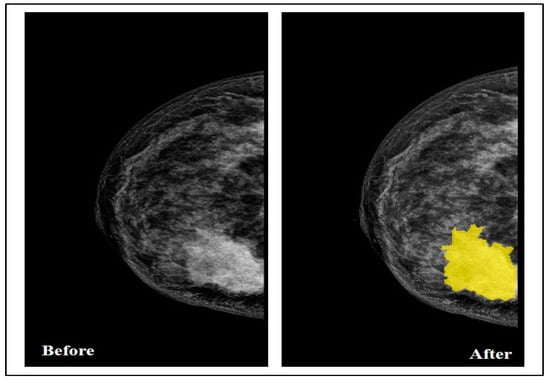

5.2. Data Annotation

By collaborating with the radiologist, the Segmenter tool in MATLAB was used in this step to manually annotate the tumor region by drawing its border in all the selected images, as seen in Figure 3.

Figure 3. Breast before and after drawing the tumor border.